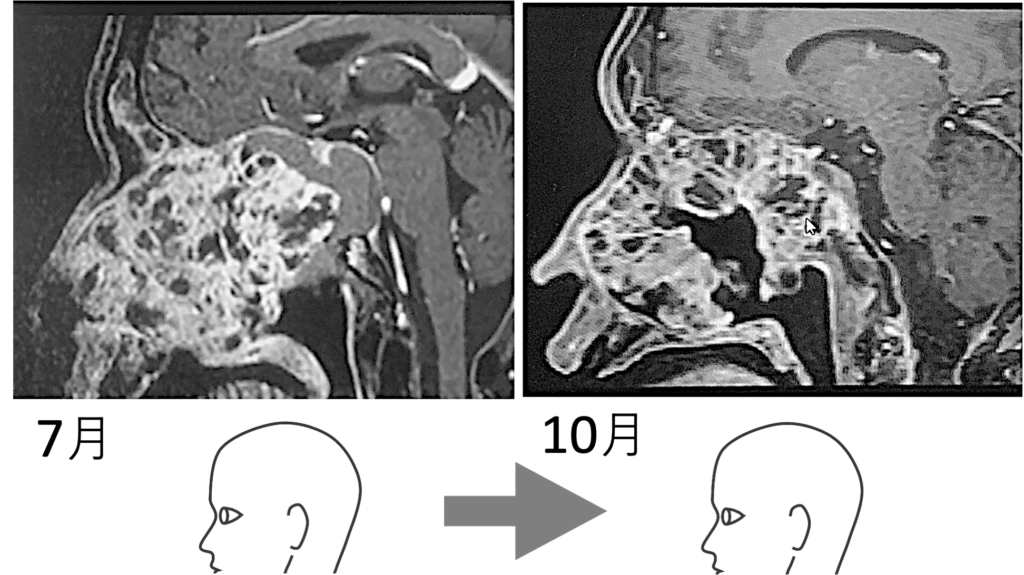

10月、画像診断でガンのコアに大きな空洞が映し出された。しかも巨大化しつつあるかに見えた全体像が縮小している。つまり真ん中に空洞ができては、その空洞が押しつぶされ小さくなり、それを繰り返しながら全体像が小さくなったのである。

下に置いた画像 (7月→10月) を見ていただくと分かるのだが、この血塊はガン中心部が崩れて排出されたものである。中心部が抜け落ちて、やがて少しずつガンの全体が縮小し、聴神経を圧迫しなくなったのである。ガン中心部から崩壊が始まったのだ。

ガン中心部が抜け落ちてできた空洞が、押されて小さくなっていくにつれて、ガン全体の輪郭も小さくなっていった。血塊が出ていないのに、7/20の血塊排出から時間を挟んで8/8に目が見えるようになった理由をそのように説明する。

すなわち、7/20血塊排出直後に画像を撮ったならば、その血塊分の空洞ができていたはずである。空洞ができ、ガンの圧力によって空洞が徐々に狭められるとともに、ガン全体のの輪郭が小さくなってきた。そう推測されるのである。

ガン中心部に空洞が出現した。あの血塊排出は、やはりガン排出だったのである。カチカチだったガンが、中心部からドロドロになり、ドロドロのガンを吐き出したのである。

画像でガンの中心部分が抜け落ちているとドクターから言われた。